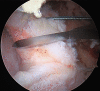

One of the primary goals of hip arthroscopy for femoroacetabular impingement (FAI) syndrome is precise removal of pathologic FAI morphology while protecting and restoring the normal soft tissue anatomy. Adequate visualization is a key foundation of precise removal of FAI morphology and varying types of capsulotomies are frequently used to achieve necessary exposure. Anatomic and outcomes studies have influenced an increasing appreciation for repairing these capsulotomies. Thus one of the central technical challenges of hip arthroscopy is achieving both goals of capsule preservation and adequate visualization. Various techniques have been described, including suture-based capsule suspension, portal placement, and T-capsulotomy. The following technique describes how the proximal anterolateral accessory portal can be added to a capsule suspension and T-capsulotomy technique to improve visualization and facilitate repair.